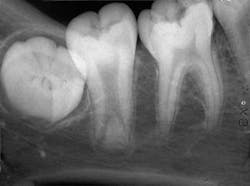

Based on the clinical examination of the patient, selected periapical radiographs, bitewings, and a panoramic film were ordered and exposed. A review of the periapical films revealed a mandibular second molar with an elongated pulp chamber and an abnormally low furcation region (see radiograph). Clinically, the second molar appeared normal in size and shape. No other abnormalities were noted on the radiograph.

Radiographic features

A taurodont is recognized by its characteristic radiographic appearance. The overall tooth length is normal, but the distance from the cementoenamel junction to the furcation is increased. The pulp chamber is greatly enlarged without a constriction at the cementoenamel junction. The rectangular shape of the pulp chamber resembles that of cud-chewing animals. The roots appear to extend only a short distance from the furcation and exhibit short root canals. Radiographically, the taurodont tends to have an overall "stretched" appearance.